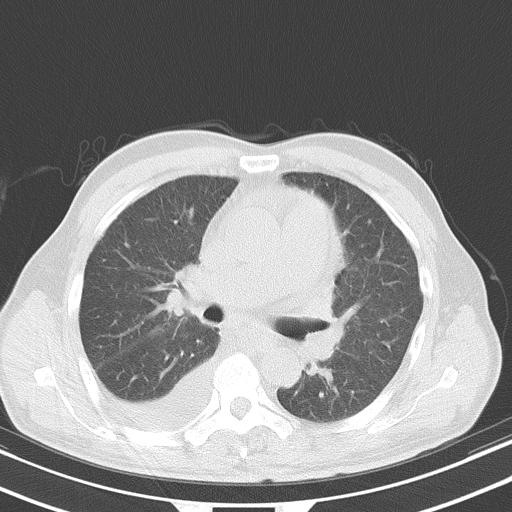

以下是引用zjzjr在2010-3-21 17:39:00的发言:[br]右下中心型肺癌并阻塞性肺炎/不张,纵膈淋巴结肿大,右侧大量胸腔积液,左侧少量胸腔积液

以下是引用zxl51642在2010-3-21 17:06:00的发言:[br]右下中心型肺癌并阻塞性肺炎/不张,纵膈淋巴结肿大,右侧大量胸腔积液,左侧少量胸腔积液,少量腹水。建议纤维支气管镜进一步检查。